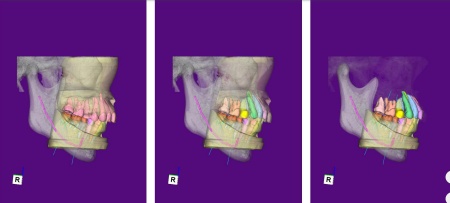

矯正期間終了後は、被せ物による治療に移行します。

上顎の前歯2本ずつと奥歯4本(左右中切歯・第2小臼歯・第1大臼歯)、下顎の奥歯7本(左第1小臼歯・左右第2小臼歯・第1大臼歯・第2大臼歯)には、見た目が自然なセラミックの被せ物「ジルコニアクラウン」を装着しました。

ジルコニアは、金属を使わないため金属アレルギーの心配が少ない点、人工ダイヤモンドと呼ばれるほどの強度をもち噛む力の強い奥歯にも適している点がメリットです。

加えて、上前歯4本(左右側切歯・犬歯)と下前歯5本(左右中切歯・側切歯・右下犬歯)は、ダイレクトクラウンによる修復を行いました。

ダイレクトクラウンとは、レジン(樹脂)を用いて直接歯の形を作り上げていく治療方法です。

歯を削る量が少ない、色や形を細かく調整しながら仕上げられる、治療後は必要に応じて微調整がしやすいなどのメリットがあります。